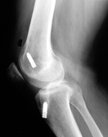

Generally the original ACL reconstruction would have used the patient's own patellar tendon (B-PT-B) or hamstrings tendon.

The problem is that if that procedure fails then the patient no longer has a fully healthy tendon for the revision surgery.

Patient and surgeon may decide on harvesting tendons from the other side, using a different tendon (like quads tendon) or using an allograft (from a tissue lab.) or an artificial ligament. It is also an option to augment a tendon procedure with artificial material.